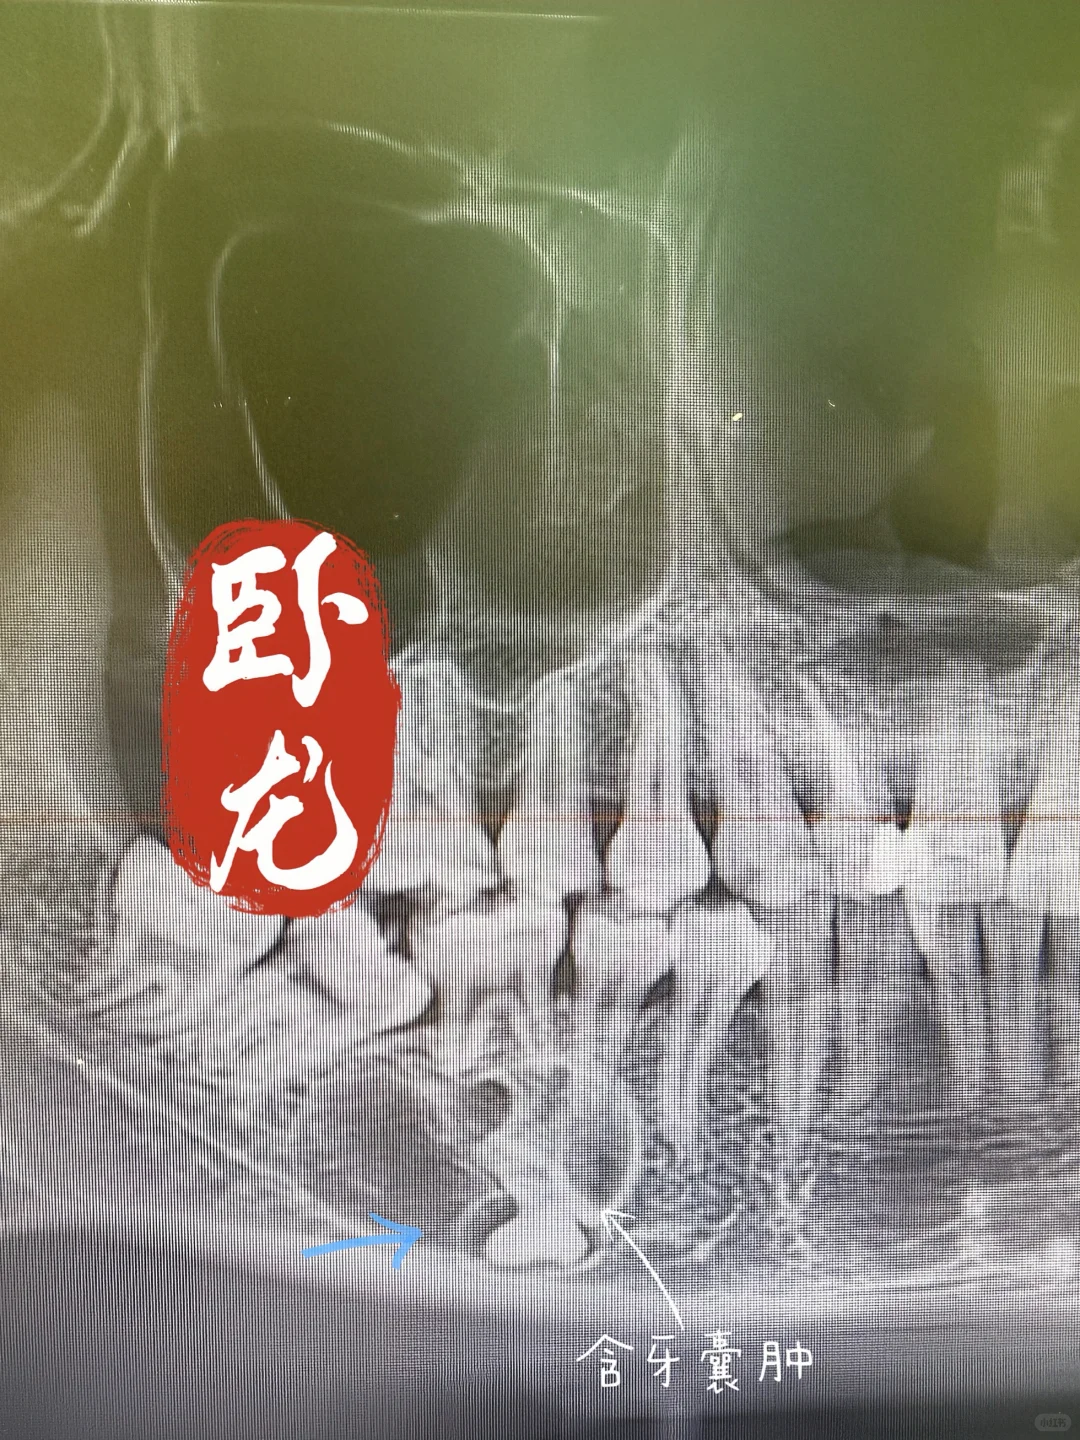

拔牙~有卧龙的地方必有凤雏!